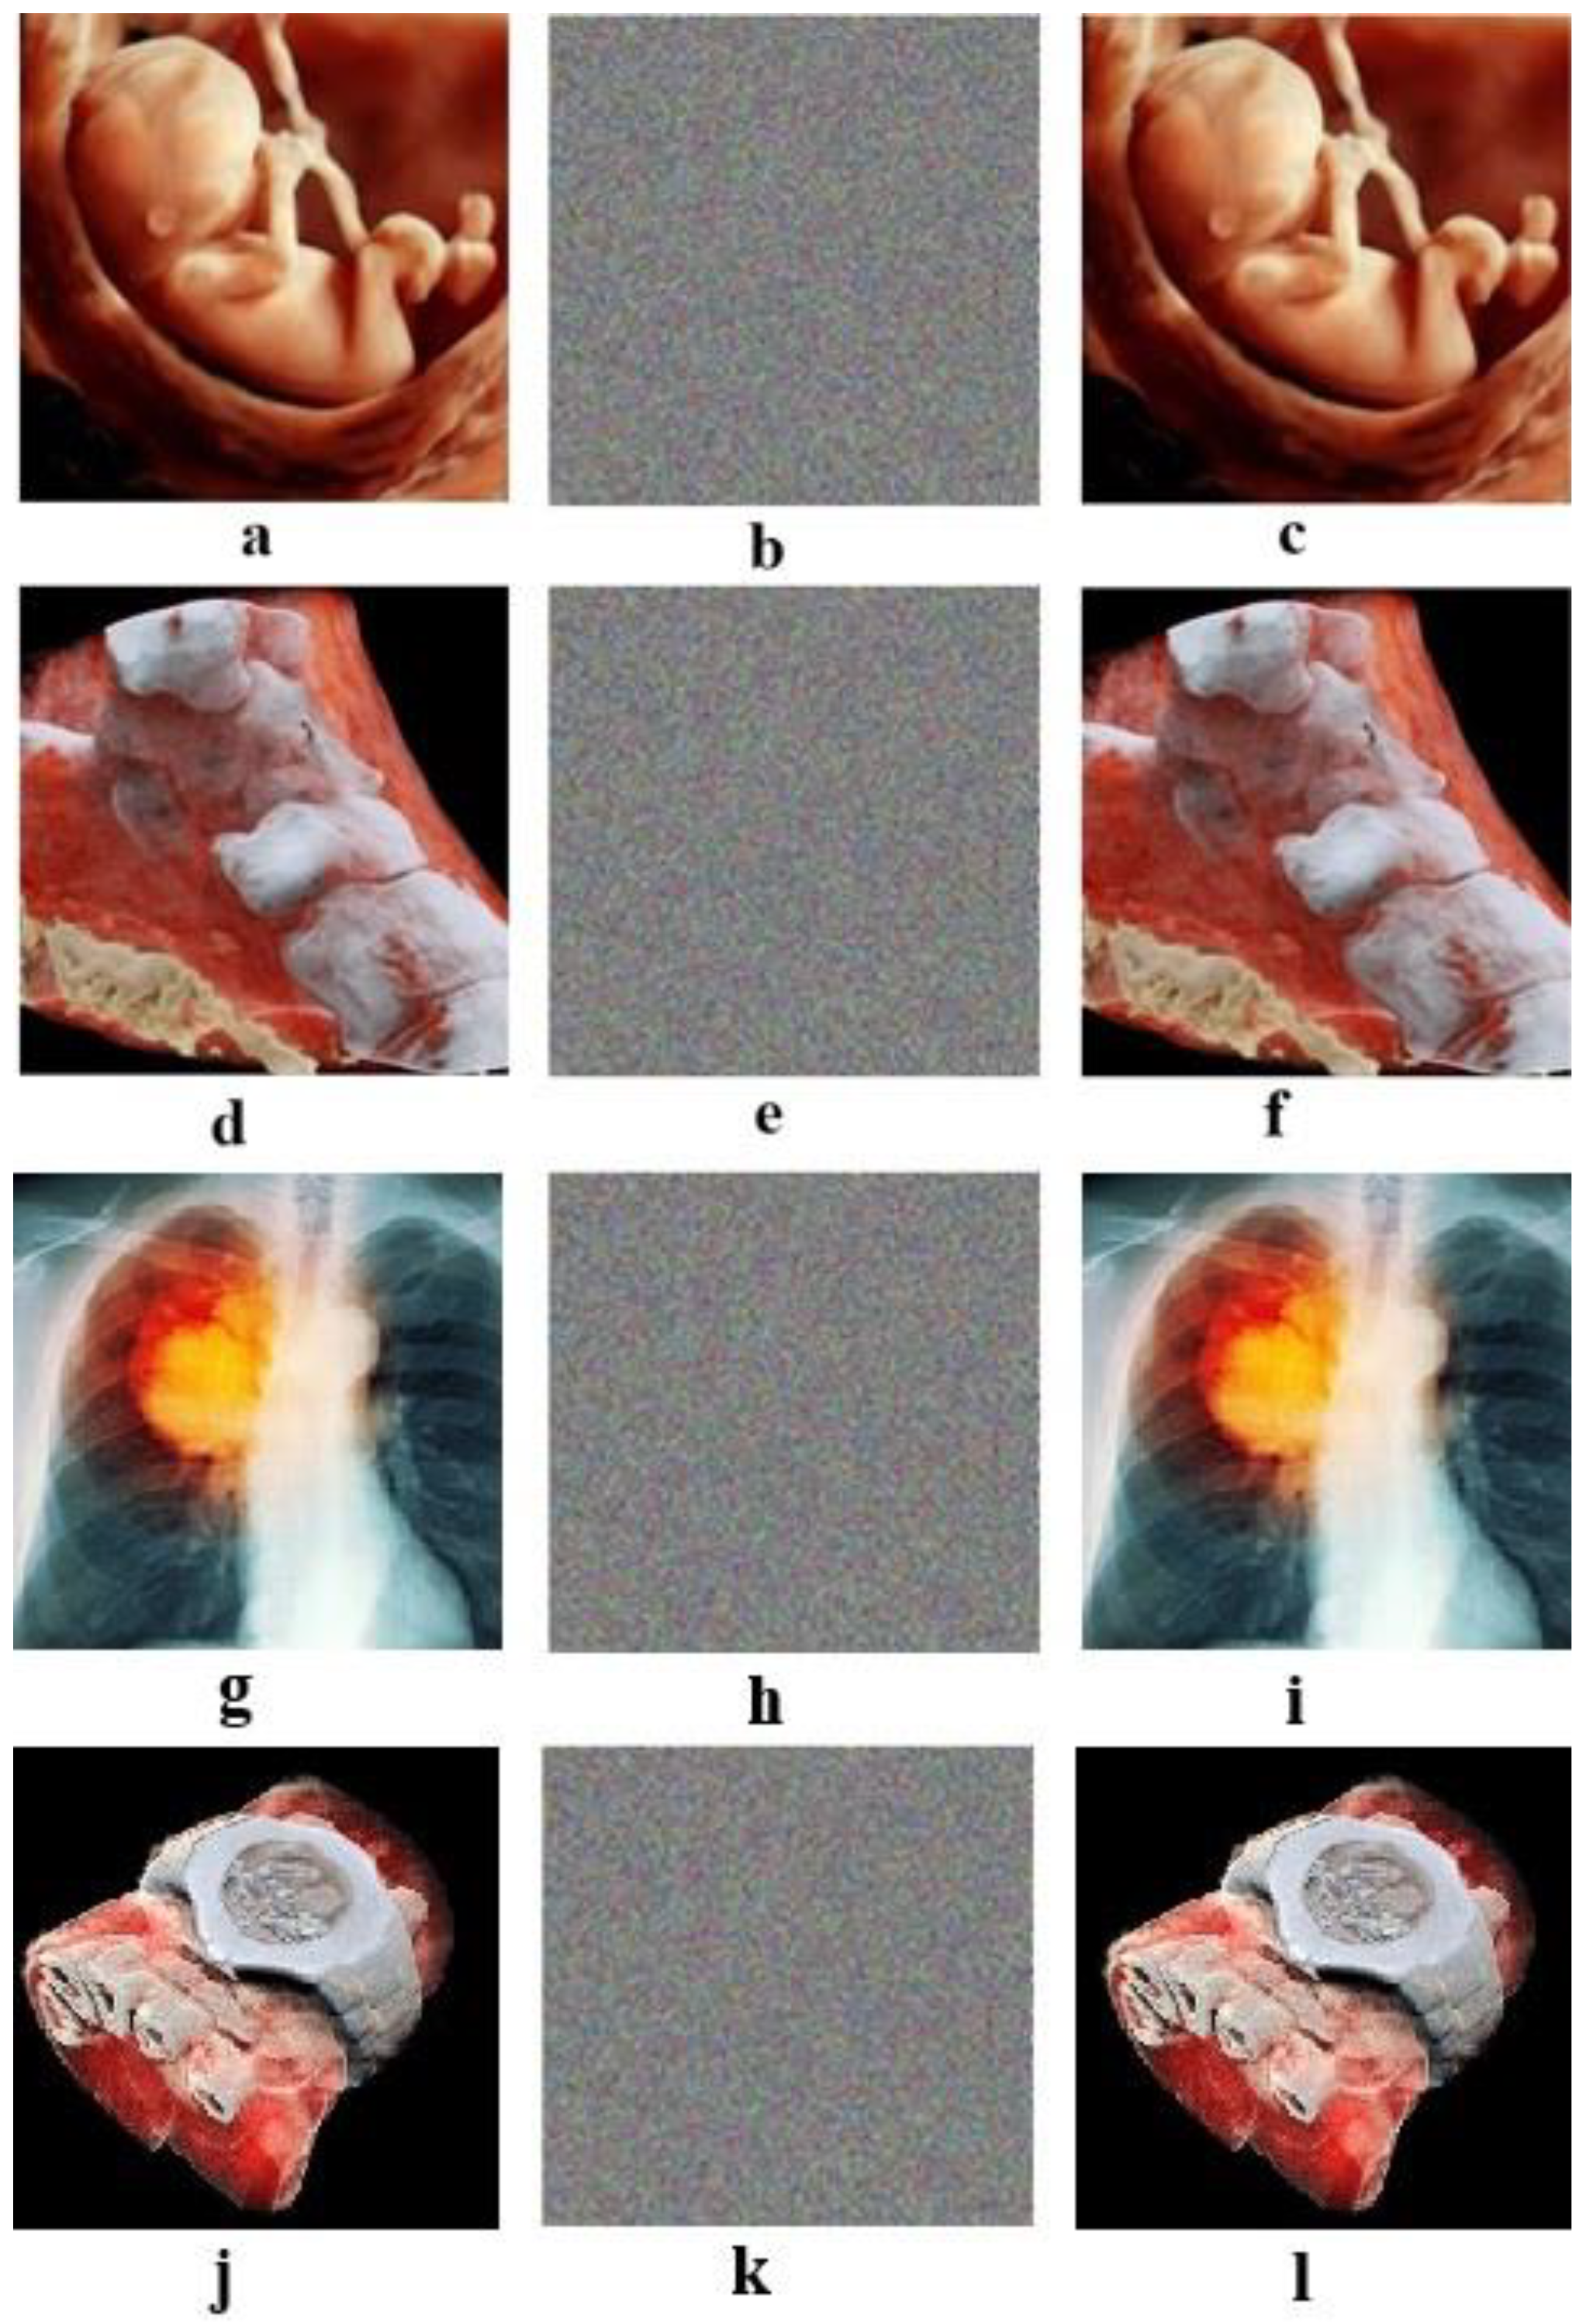

For example, four color images 256 × 256 in size have been selected as the plain images. In Figure 3, images b, e, h, and k are images that are encrypted by the proposed algorithm for the plain images a, d, g, and j, respectively; and images c, f, i, and l are the decrypted images.

(a,d,g,j): Plain images. (b,e,h,k): Respective encrypted images. (c,f,i,l): Respective decrypted images. Initial values for all images: (a0 = 0.1314, b0 = 0.5214, c0 = 0.3698, and d0 = 0.8419). Values of the chaotic system: Image (a): sha256 = ‘9ADBBFB88CFD90C23CE114E47402054E6DDC4182510E80980EA7151CD11E6D18’, image (d): sha256 = ‘8BF6A886E4B58D2B530749EE9BAB54A3C360D406DC5B901CC169D7870FA3CA09’, image (g): sha256 = ‘49A22186DB65786789CD1391CDE4D9737039E758F39A45C59D8338DE05353337’, and image (j): sha256 = ‘6EB1ADE45F27A67E09A25265835F05BC11E057255DA81359299631F4724936C8’.